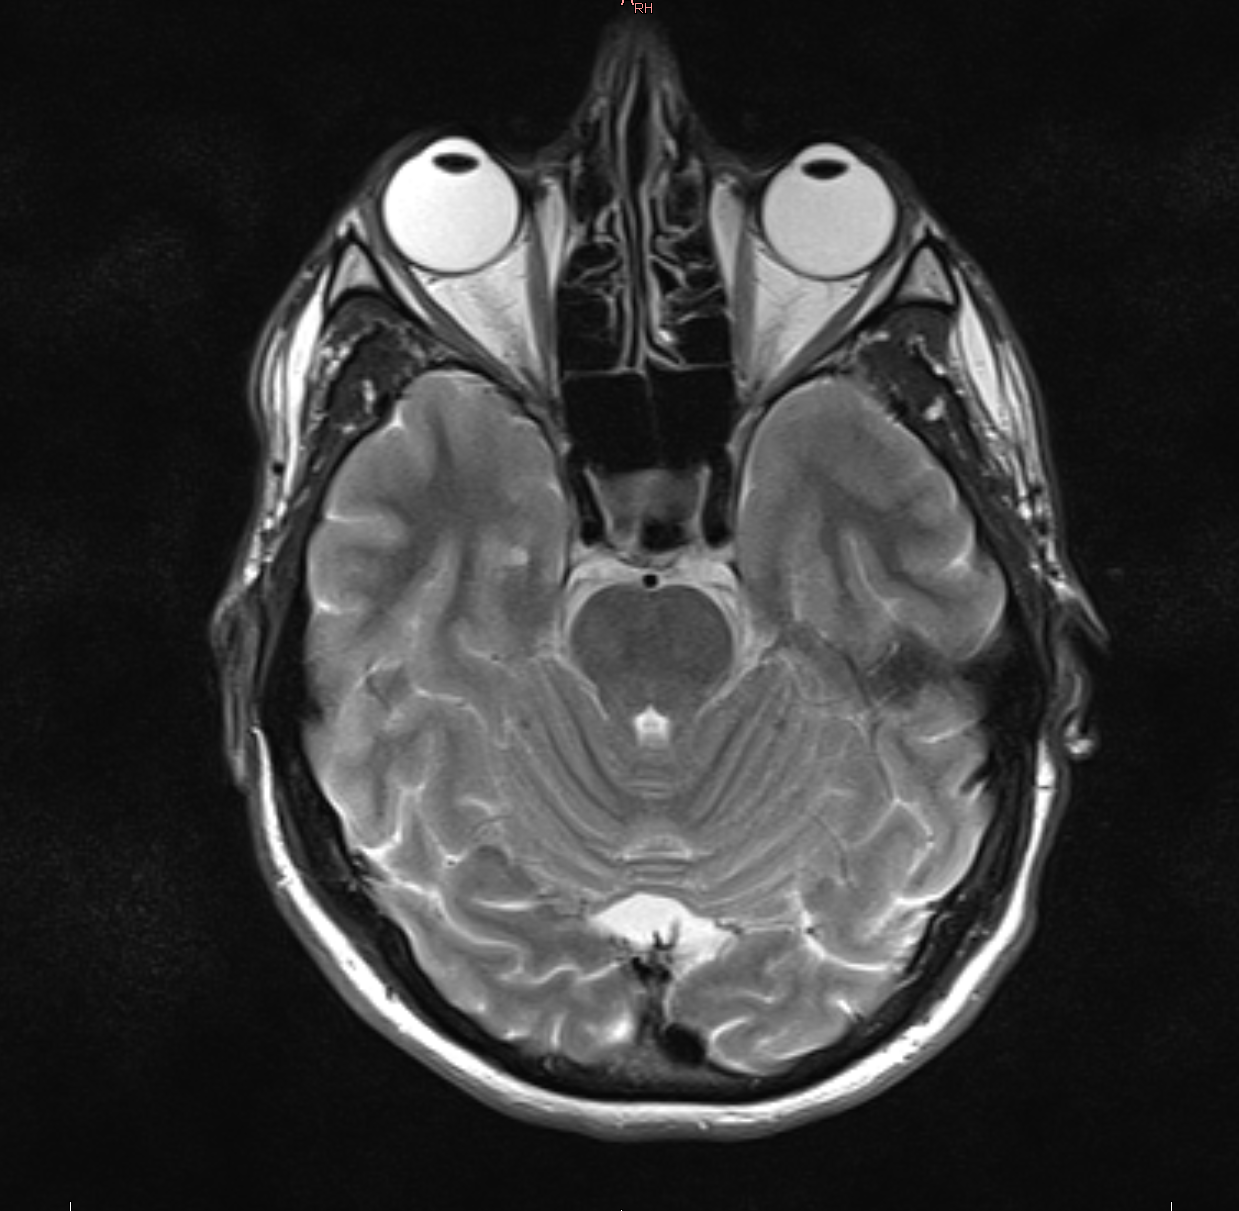

Гастроэнтеролог, Лор, Эндокринолог - без патологий. Невролог зафиксировала некоторые проблемы, вроде сжиженного небного и глоточного рефлексы, и направила сделать мрт головы и шеи. На МРТ ничего критичного не было - субатрофические изменения головного мозга и остеохондроз шейного отдела позвонка. Собственно, на этом моменте все и застопорилось. После этого я ходил к платным неврологам, но особого успеха там не сыскал.

Подозревают рассеянный склероз, жду направление в местный центр РС.

Началось все с недельного головокружения в конце февраля. Головокружение прошло само, к тому моменту, как я получил результаты МРТ, обнаружены три очага демиелинизации.

Вроде бы состояние не ухудшается, но по-прежнему сохраняется неуклюжесть в походке, незаметная со стороны, ухудшение контроля левой ноги в области стопы, движения ощущаются не непрерывными и плавными, а будто рваными, небольшая, но постоянная усталость.

Могут ли быть очаги демиелинизации без диагноза РС, как разовое явление без прогрессирования?

3 года назад делал МРТ - не обнаруживались.

Алсо, терапевт направила на анализы ВИЧ/сифилис/гепатит B,C - не обнаружены.